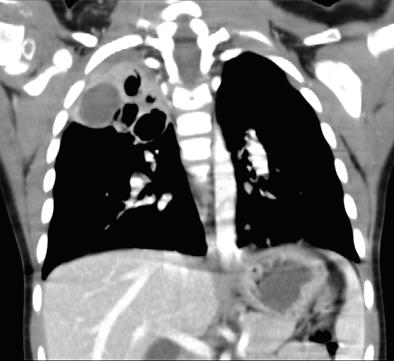

основна роля в причиняването на тежка и/или ус ложнена ППО. Значителен брой деца с ППО, причинени от атипични бак терии, показват сложно протичане, поради наличието на плеврален из лив[5] РИСКОВИ ФАКТОРИ И ЗАЩИТНИ МЕХАНИЗМИ НА ОРГАНИЗМА Микроорганизмите са разви ли разнообразни механизми, кои то благоприятстват колонизация та им в гостоприемника. Например, Парапневмонични усложнения – случаи от практиката Ю. Димитрова, Д. Хасанова, И. Цочева Отделение по педи атрия, УМБАЛСМ “Н. И. Пирогов” - София Придобитата в обществото пневмония все още остава честа причина за заболяемост и смърт ност в световен мащаб. Честотата е най-висока при деца под 5 години. S. pneumoniae и H. influenzae са водещите причинители на бактериална пневмония. При деца над 5-годиш на възраст зачестяват атипичните бактериални причинители - Mycoplasma pneumoniae и Chlamydophila pneumoniaе. Най-често тежките пневмонии, които протичат с усложнения, са вследствие на бактериални причинители и се изявяват с парапневмоничен излив, емпиема, мултилобарно заболяване, кавитарен абсцес, некротизираща пневмония, пневмоторакс, и бронхоплеврална фистула. ПЕДИАТРИЯ Ключови думи: Деца, ППО, парапневмонични усложнения.

В световен мащаб S. pneumoniae и H. influenzae са водещите причинители на бактериална пневмония. Най-чес тите патогени, идентифицирани при последното активно наблюдение на населението в Съединените щати, са човешки риновирус, грипен вирус и Streptococcus pneumoniae[4]. Метицилин-резистентен Staphylococcus aureus (MRSA), който първоначално е определян като но зокомиален патоген, все по-често се открива

ност [СПИН] и тежка съпътстваща бе лодробна болест, като бронхиекта зии, кистична фиброза и хронична обструктивна белодробна болест [ХОББ])[8]. Известно е (главно на база та на проучвания на пунктати от бе лите дробове, проведени в развива щите се страни), че леката и умерена ППО се причинява главно от вируси, особено през първите години от жи вота, докато повечето случаи на теж ка ППО се причиняват от бактерии. Въпреки това е доказано, че грипни те вируси и респираторно-синцити алният вирус играят

в общността, където се на рича придобит в общността MRSA. Същият може да доведе до тежки бе лодробни инфекции, включително некротизираща и хеморагична пнев мония[7] Инфекцията с Pseudomonas aeruginosa е рядка при липса на спе цифични рискови фактори (скорош но антибиотично лечение, синдром на придобита имунна недостатъч